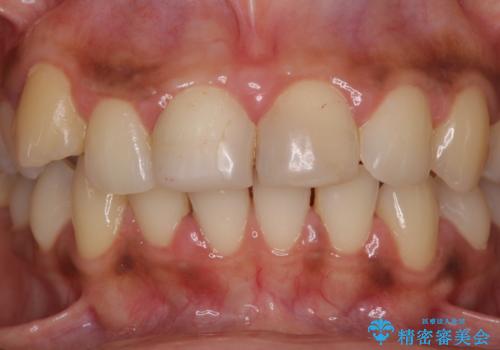

- 上の前歯2本の審美障害を気にして来院された患者様です。樹脂が無造作に充填されており、色合いも形態も不自然で、歯肉も腫れているため、オールセラミッククラウンにて補綴することとしました。

充填されたレジンを取り除いたところ、歯肉の炎症による出血が認められました。セラミッククラウン装着後は歯肉が腫れることもなく、仕上がりも自然な歯のようになり、患者様には大変満足していただきました。